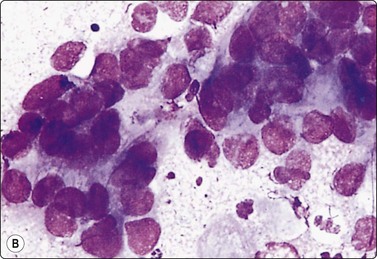

Adenocarcinoma (Figs 11.9-11.11)

image

Fig. 11.9 Adenocarcinoma (pancreas)

Very well-differentiated adenocarcinoma presenting as cohesive, monolayered epithelial sheets; note nuclear crowding, overlapping and nuclear atypia present focally (H&E, HP).

image image

Fig. 11.10 Adenocarcinoma (pancreas)

Well-differentiated adenocarcinoma; relatively mild nuclear atypia, but nuclear crowding and some dissociation, and in B a tendency to microacinar arrangement (A, MGG, HP; B, H&E, HP).

Fig. 11.11 Adenocarcinoma (pancreas) moderately differentiated

(A) Sheets showing disorganization and nuclear pleomorphism; background of necrotic debris (H&E, IP); (B) Disorganized clusters with some acinar arrangements (MGG, HP).

Criteria for diagnosis33,70-73

Disordered monolayer sheets, microglandular patterns, nuclear crowding; loss of cell cohesion,

Nuclear criteria of malignancy with contour irregularity and fairly distinctive margination of chromatin,

Moderate amount of cytoplasm, often mucin vacuoles, indistinct cell borders,

Evidence of necrosis, mitoses, macronucleoli and hyperchromasia in poorly differentiated forms.

Almost all adenocarcinomas arising in the pancreas are of ductal origin, without unique features permitting absolute distinction from carcinomas arising in the biliary tree. The characteristic FNB pattern is of crowded ‘drunken’ monolayered sheets, with moderately tall columnar palisading cells at luminal edges. Smaller aggregates commonly show rounded glandular structures with feathered edges, or three-dimensionality. Cytoplasmic borders may be very well demarcated in better-differentiated forms; in other cases, the monolayer sheets appear syncytial. The diagnosis of malignancy ultimately depends on nuclear features, which range from very subtle alterations to overly malignant criteria with decreasing differentiation (Figs 11.9-11.11). In an assessment of individual criteria by regression analysis, Cohen and colleagues extracted as most important: anisocytosis (4 : 1), nuclear enlargement and molding, with combined sensitivity of 98% using all three criteria to distinguish malignant from benign.70 In a similar study, Robins, Katz and Evans ascribed major status to nuclear crowding, contour and chromatin irregularity, minor status to single cells, mitoses and enlarged nuclei,33 requiring two major, or one major and two minor criteria for the definitive diagnosis of malignancy. Focusing specifically on the most challenging area, the recognition of well-differentiated carcinoma, Lin and Staerkel listed the following features: nuclear enlargement > 2 rbc (99%), anisonucleosis 4 : 1 (97%), nuclear membrane irregularity (97%), and crowding/overlapping/three-dimensionality (92%).73